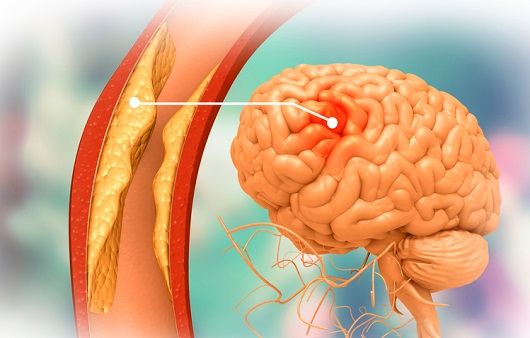

뇌경색의 주된 이유가 되는 것은 혈전이지요. 혈전이란 혈관 속에 피가 굳어진 덩어리를 얘기하는데 이것이 혈관을 막는 것이 뇌경색에 큰 영향을 줄 수 있습니다. 평균적으로 많이 발생하는 연령대는 5~60대이지요. 뇌경색은 양쪽 뇌에 모두 나타나는는 것이 아니라 주로 한쪽 뇌에만 발생하지만, 주로 한쪽 팔다리가 마비되었다거나 얼굴 근육이 굳어버리기도 해요. 그렇기에 뇌경색 초기증상이 발생한다면 민첩하게 대응를 해야 하겠습니다.

또 뇌경색의 까닭은 혈관의 협착을 유발시키는 동맥경화증이고요. 동양에서는 뇌내동맥경화증이, 서양에서는 경동맥동맥경화증이 많이 나타나고다. 그리고 흡연, 고지혈증, 당뇨병, 고혈압, 건강에 옳지 않은 식습관, 스트레스 등도 뇌경색을 발생시키는 위험요인입니다.모든 질병에 단일 이유가 되는 것이 없듯이 뇌경색도 단일 이유가 되는 것이 아닐 수 있고요.